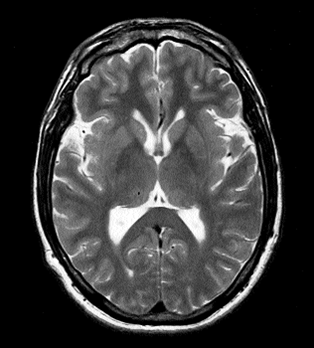

Picture2 Published at 314 × 348 in Fifty Shades of Grey [matter] ~ interpreting MRIs « Previous Next » my ventricles are INTENSE and I’m angry about it, T-2